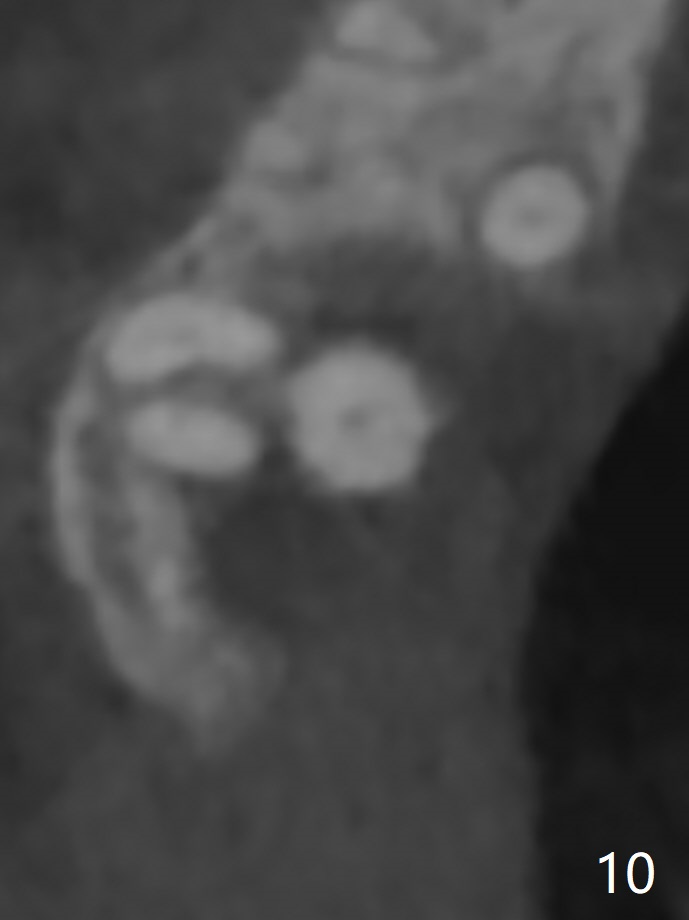

45岁女右上7严重骨质吸收终于开始出现症状(图一),虽然邻牙(6)骨质吸收也明显(图二,四,六,八,十),但是保留它,远中颊侧(DB),腭侧(P)根成为骨粉(图三,五,七,九,十一:红圆圈)支架。